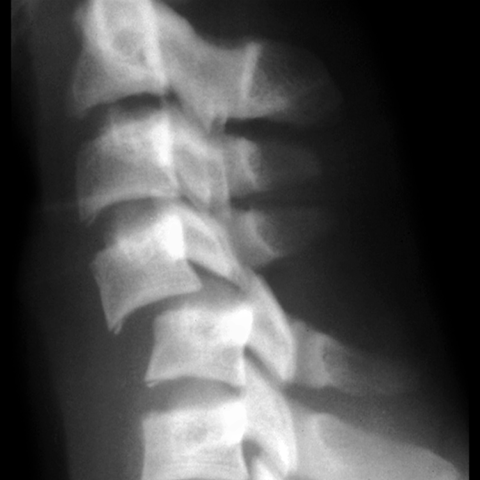

Hyperflexian injury of cervical spine, plain film [2 of 2]